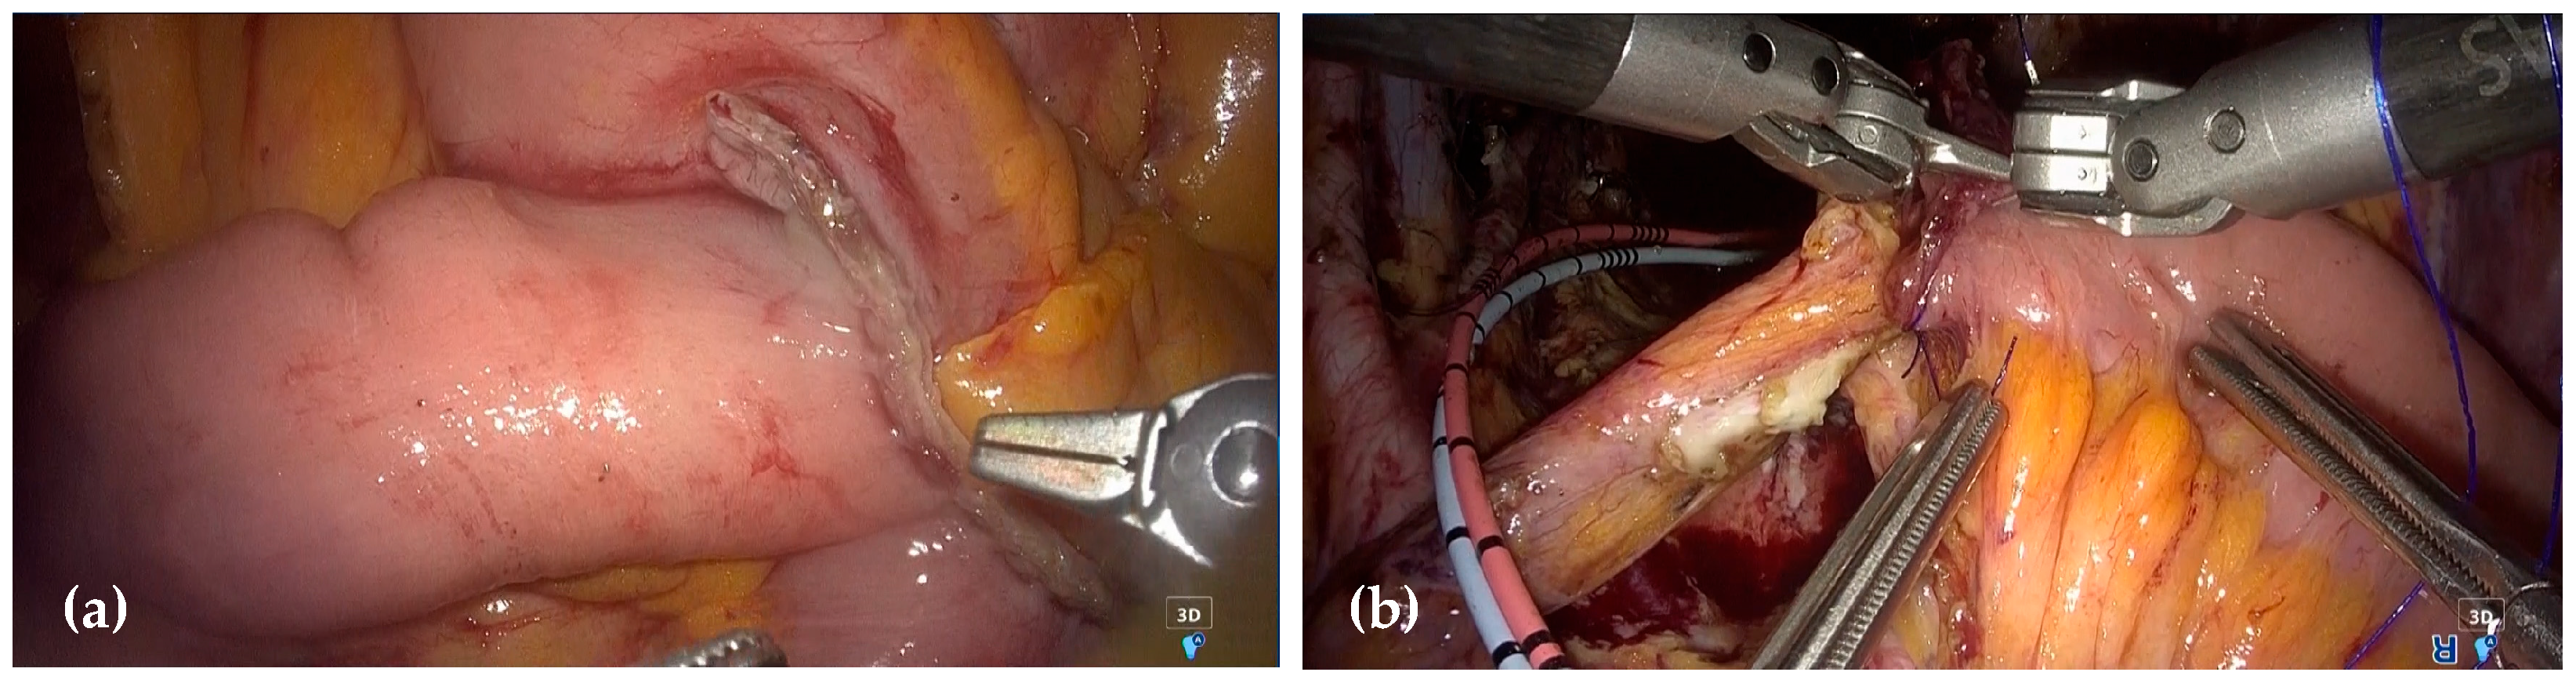

2.3. Surgical Procedure